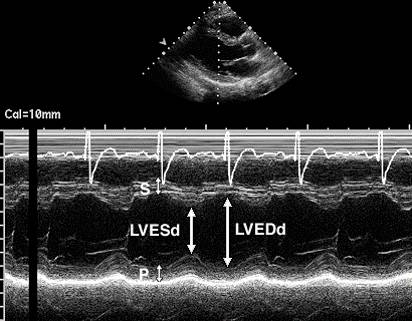

V =7D3/(2.4+D) (Teichholz校正公式)

EF(%) =(Vd-Vs)/Vd